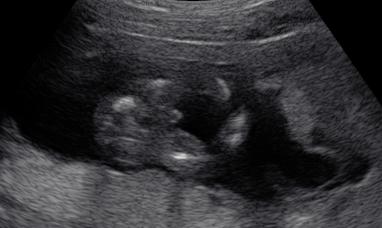

Nevim, jak je u vas videt to pohlavi, ale tady to vypada jako jasny chlapecek, prikladam obrazek.

Luci tak takové foto pindíka máme taky tak myslim,že by to ti kluci měli být:)my už teda doma jednoho máme takže zase by to bylo jednodužší s oblečením a pokojíčkem,protože děti budou mít pokojíček jeden dohromady.